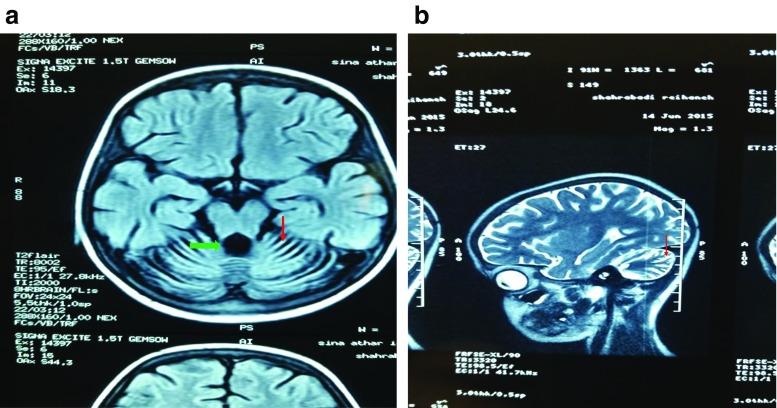

Ataxia-telangiectasia (A-T), a rare inherited disorder, usually affects the nervous and immune systems, and occasionally other organs. A-T is associated mainly with mutations in the ataxia telangiectasia mutated (ATM) gene, which encodes a protein kinase that has a major role in the cellular response to DNA damage. We report here a novel ATM mutation (c.3244_3245insG; p.His1082fs) in an 11-year old female. This subject presented with typical features, with the addition of chest manifestations including mediastinal lymphadenopathy and diffuse bilateral micronodular infiltration of the lungs, along with a high EBV titer. The subject died as a result of rapid B-cell lymphoma progression before chemotherapy could be initiated. This case highlights the need for the rapid diagnosis of A-T mutations and the detection of associated life-threatening outcomes such as cancers.